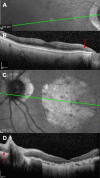

Purpose: To investigate outer retinal tubulation (ORT) using spectral domain optical coherence tomography (SD-OCT) and an adaptive optics scanning laser ophthalmoscope (AOSLO). To document the frequency of ORT in atrophic retinal conditions and quantify ORT dimensions versus adjacent retinal layers.

Methods: SD-OCT images were reviewed for the presence of retinal atrophy, scarring, and/or exudation. The greatest width of each ORT was quantified. Inner and outer retinal thicknesses adjacent to and within the area of ORT were measured for 18 patients. AOSLO imaged ORTs in five subjects with direct and scattered light imaging.

Results: ORT was identified in 47 of 76 subjects (61.8%) and in 65 eyes via SD-OCT in a wide range of conditions and ages, and in peripapillary atrophy. ORTs appeared as finger-like projections in atrophy, seen in the en face images. AOSLO showed some ORTs with bright cones that guide light within atrophic areas. Multiply scattered light mode AOSLO visualized variegated lines (18-35 μm) radiating from ORTs. The ORTs' width on OCT b-scan images varied from 70 to 509 μm. The inner retina at the ORT was significantly thinner than the adjacent retina, 135 vs.170 μm (P = .004), whereas the outer retina was significantly thicker, 115 vs. 80 μm (P = .03).

Conclusions: ORTs are quite common in eyes with retinal atrophy in various disorders. ORTs demonstrate surviving photoreceptors in tubular structures found within otherwise nonsupportive atrophic areas that lack retinal pigment epithelium and choriocapillaris.